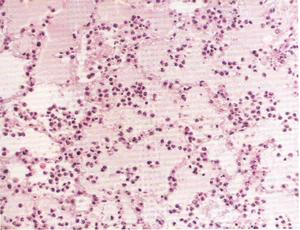

蛋白尿和血尿本品的毒性較慶大黴素和卡那黴素輕,不良反應發生率約2%~3%。臨床套用後少數患者可出現血尿素氮及轉氨酶輕度增高,偶有耳鳴、聽力暫時減退、蛋白尿、血尿、發熱、頭痛、麻木、食慾減退、腹瀉、皮疹等。肌注處疼痛較多,但一般可以忍受。

敗血病檢查血象:白細胞總數大多顯著增高。

細菌塗片:膿液、腦脊液、胸腹水、瘀點等直接塗片檢查,也可檢出病原菌,對敗血症的快速診斷有一定的參考價值。